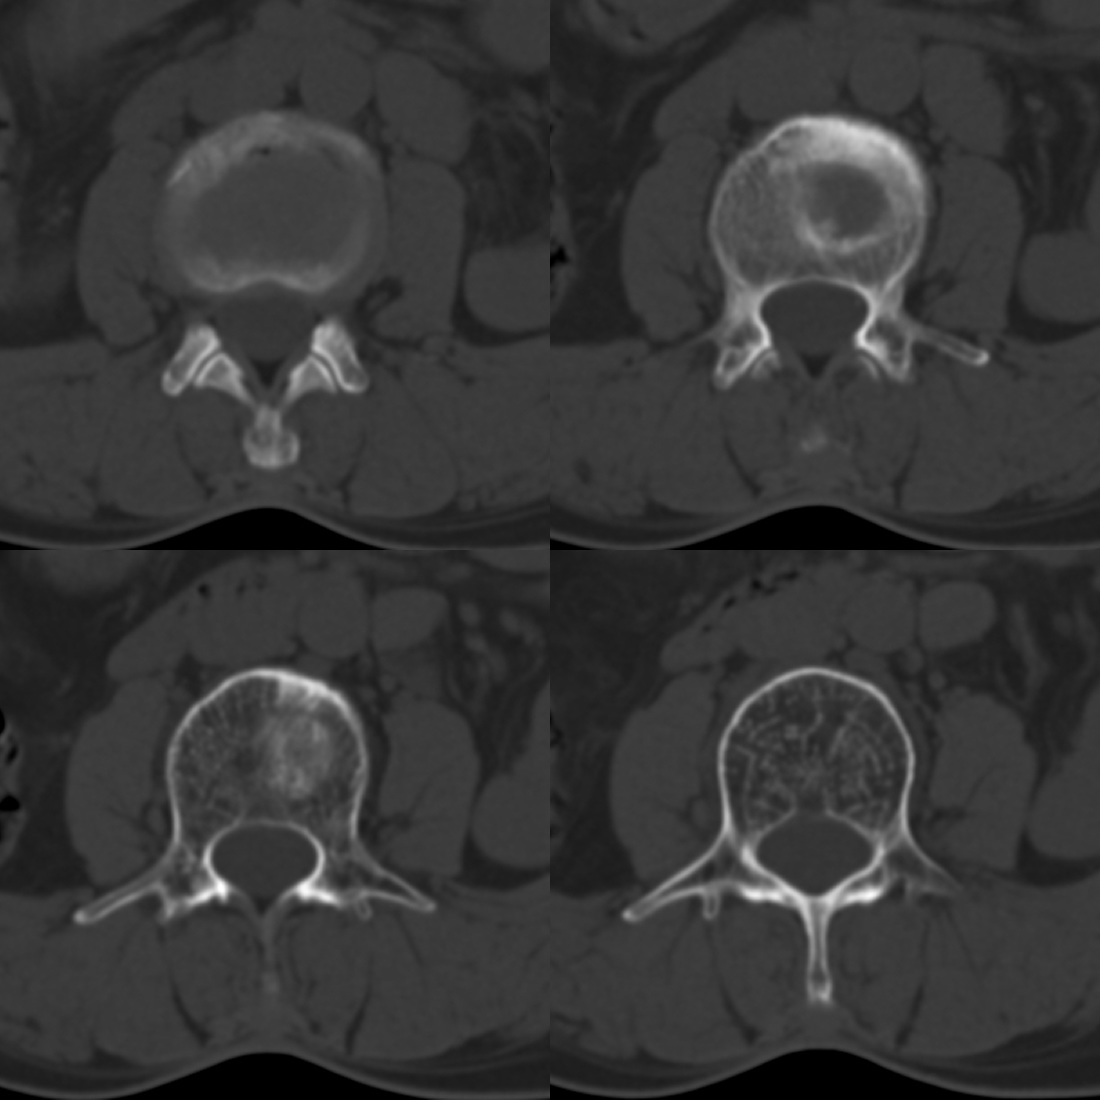

标题: CT14702:52F,椎间盘。

52岁女性,腰痛,活动守限,有腰部外伤史。请教各位战友,应该怎么报。

l2/3椎间隙

骨窗:

许莫氏结节,退变。

1、腰3椎体斯莫氏结节;

2、腰椎骨质增生。

1)l3椎体上缘许莫氏结节。2)腰椎退行性改变。

腰1椎压缩性骨折未除。

l3椎体上缘许莫氏结节。腰椎退变。